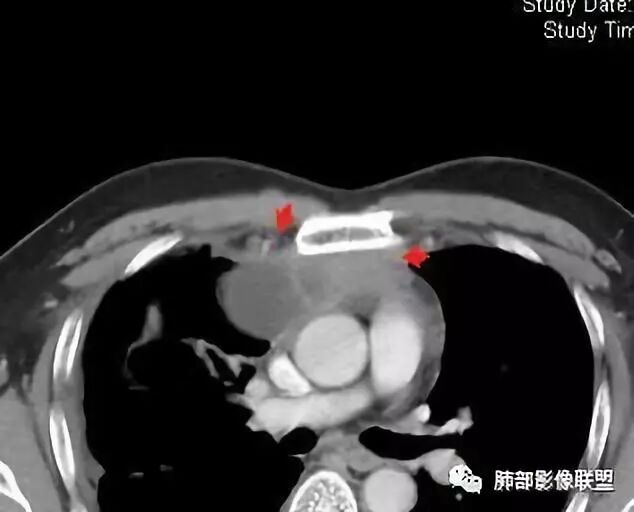

穿越七海的风:右前纵隔占位,恶性肿瘤,生殖来源?右肺实变是占位or肺不张?考虑为部分肺不张FeNo:右前纵隔占位,右肺结节,胸膜凹陷,小尾巴,右肺不张,考虑恶性杨旭华:恶性,前纵隔肿物,与血管关系密切,上腔静脉变窄,右肺野一元论考虑叶间裂增厚,恶性胸膜间皮瘤可能大小丽:到底是纵隔来源还是胸膜来源?我怎么倾向于胸膜来源,和叶间胸膜关系密切,而且纵隔内上腔静脉是向内侧推移。胸膜肿瘤(间皮瘤?SFT?)包裹性胸腔积液?马春平(张家港市一院胸外科):前纵隔占位,左无名受压,右大量胸腔积液可能是胸导管汇入处侵犯受压,考虑纵隔鳞癌孙冰伟:右上纵隔占位,也感觉和叶间胸膜关系密切,右侧胸膜局限性增厚,考虑恶性可能性大灵:前纵隔占位,血性胸水,胸膜凹凸不平,查见肿瘤细胞,结合免疫组化考虑胸腺癌。鉴别胸膜间皮瘤。采莲:右前上纵膈旁可见类圆形肿块,纵隔血管内移,感觉来源于胸膜,肿块内密度低,似水样密度,右侧胸膜广泛增厚,少量胸腔积液。心包少量积液。考虑胸膜间皮瘤,鉴别肺癌并胸膜转移?水晶石头:患者中年男性,胸闷15天。有“高血压、慢性肾小球肾炎”病史。查肿瘤标志物正常,胸水提示渗出液,胸水病理查见瘤细胞。胸部CT:右肺上叶后段结节、斑片影,见胸膜牵拉、包裹积液及部分纤维条索灶,似见卫星灶,右侧胸膜增厚。前纵隔脂肪密度增厚,右侧可见类圆形低密度(液体)肿块,边缘光滑。综合考虑右肺腺癌并胸膜转移,结核可能。周太狼:考虑纵隔胸膜来源肿瘤,恶性,胸膜间皮瘤伴转移?徐飞:中年男性,影像为右侧胸腔及叶间积液,叶间胸膜增厚轻度强化。前纵隔右侧心缘旁团块,可见坏死。胸水见癌细胞,综合考虑恶性,胸腺癌伴转移。小赵:中年男性,血性胸水,常规查见癌细胞,李凡他实验阳性。胸部CT示前纵隔见不均匀密度影,与邻近大血管分界不清,囊变坏死明显,增强扫描呈不均匀强化,心包及右侧胸膜增厚,并心包及右侧胸腔少量积液。综合考虑胸腺癌。右肺中叶病变周围见多发纤维条索,支气管部分进入病灶,考虑炎性病变。流心明智:患者,男性,50岁。胸闷15天。高血压20年,慢性肾小球肾炎15年。肿标正常,胸水提示渗出液,胸水查见癌细胞。胸部CT:右肺肿块影,斑片影,索条影,可见胸膜牵拉、多发包裹积液,纵隔上腔静脉受累,心包受累。综合考虑:ROSE似腺?考虑右肺腺癌并胸膜转移,心包受累。鉴别胸腺Ca、淋巴瘤,纵隔病变不懂,等老师们精彩分析。王秀仙:前纵膈囊实性肿块,与纵膈分界不清,心脏大血管及上腔静脉受压向内后移,右侧后胸膜、侧胸膜增厚,右侧叶间裂不规则增厚,心包积液,根据腔静脉移位情况,考虑纵膈胸膜来源恶性肿瘤,胸膜间皮瘤?鉴别胸腺癌并胸膜转移。高广飞:上纵隔占位,右侧叶间胸腔积液,需考虑恶性自信人生:多发囊实性病灶,包裹性积液,考虑胸膜来源 只是没有看到壁结节,恶性胸膜间皮瘤巴伟:前上纵隔占位,胸膜及心包结节,考虑胸腺瘤或癌,右肺病灶,先考虑陈旧炎性病变。Lenle董:前纵隔占位,部分边缘模糊,病灶内囊变?坏死?上腔静脉受侵,考虑胸腺癌;叶间片状影,强化明显,炎性考虑。常志强:前纵隔囊实混杂密度肿块,边界不清,实性部分强化明显,结合胸水内见癌细胞,考虑恶性肿瘤伴转移。飞鹰行动:前纵隔占位,软组织密度及囊性密度,实性部分密度均匀,致密,病灶与周围血管分界不清,增强后病灶强化有类似不温不火强化,部分血管受侵犯,右肺见肿块样病变及条索状病变,一元论,考虑淋巴瘤,二元论,考虑胸腺瘤B2—B3伴右肺病变。尽量一元论考虑,淋巴瘤可能。看图说话:右肺索条病灶,边缘膨隆,胸膜牵拉,考虑右肺癌伴胸膜转移。晨:前纵隔囊实性肿块,与纵隔分界不清,右侧后胸膜、侧胸膜增厚,右侧叶间裂不规则增厚,考虑纵隔胸膜来源恶性肿瘤,考虑胸腺癌并胸膜转移。丽:中年男性,前纵隔囊实性肿块,呈偏心性生长,临近大血管受压推移,增强后实性部分不均匀强化,心包可见条形积液,考虑胸膜来源恶性肿瘤,胸腺癌可能大。另右肺多发斑片状高密度影及实变密度影,实变影呈均匀强化,右侧胸膜局限性增厚,考虑炎性病变。小飞:右前纵隔囊实性占位,实性部分明显强化,右侧叶间胸膜增厚,右侧胸腔积液,心包积液,考虑恶性胸腺瘤!尘缘:支持恶性胸腺瘤(囊实性肿块,实性强化,且侵犯纵隔,脂肪间隙模糊)伴肺内及胸膜转移。浪迹天涯:考虑侵袭性胸腺瘤——胸腺前纵隔占位,周围脂肪间隙模糊不清。尘缘:不除外另一种可能:二元,肺内腺癌合并胸膜转移,纵隔的畸胎瘤可能。一米阳光:晨读中年男性,右肺结节影,叶间裂及胸膜增厚牵拉,右侧胸水。心包多发结节改变。胸水查见癌细胞。考虑,腺癌并转移。鉴别,胸膜间皮瘤并转移前纵隔囊实性占位,二元考虑。心灵鸡汤:老年男性,右肺中叶外段长条状软组织密度影,边缘膨隆,邻近胸膜牵拉,部分胸膜有栽脏,右中叶外侧段支气管堵塞,常规考虑恶性肿瘤,腺癌可能,结核、鳞癌不除外,另右肺上叶斑片影,小叶性肺不张?右前纵隔囊实性不规则形密度影,其内见部分脂肪样极低密度影,与邻近血管边界不清,心包外膜有侵犯,增强未见纵隔窗平扫,实性及分隔见增化,其内低密度影未强化,考虑低度恶性纵隔肿瘤,间皮瘤可能,畸胎瘤、淋巴瘤待排,建议支气管镜及穿刺活检。曹志勇:右前纵隔考虑来源于胸膜的恶性肿瘤,右肺内病灶考虑鳞癌,二元德芙~云味:中年男性,右肺见结节、斑片影,右侧包裹积液、胸膜牵拉,纤维条索,前纵隔囊性占位,考虑腺癌、并转移。欧阳英:右前中纵隔囊实性肿块及右肺内结节灶,支持恶性肿瘤,胸腺癌并肺内转移可能张延军:前纵隔见不规则软组织影,密度不均,右侧缘见囊变区,纵膈及侧胸壁胸膜增厚,增强呈不均匀强化,右肺中叶见结节灶,近段支气管阻塞,叶间胸膜不规则增厚,考虑1:右肺中叶腺癌伴纵膈及胸膜转移;2:前纵膈侵袭性胸腺瘤并胸膜侵犯,中叶炎性改变?彭君:老年,前纵隔占位 ,坏死边缘清, 侵犯心包 右侧胸膜及叶间胸膜结节 ,少量胸水, cea不高 ,考虑恶性, 间皮瘤可能 ,转移待除外。毛勤香:恶性没问题,胸水查见癌细胞,一元还是2元,右肺中叶肿块,边缘毛糙,局部似有毛刺,周围有粘连,右侧胸膜腔少量积液,胸膜增厚多发结节,含叶间裂结节,纵膈脂肪间隙模糊,纵膈胸膜增厚,心包增厚积液,右前那个类圆形低密度肿块,纵膈血管内移,我考虑胸膜来源可能性大,综合考虑,一元肺腺癌并多发转移,二元考虑胸膜间皮瘤并多发转移,肺内炎症不张。

南边:大家看看前纵隔的病灶,符合肿瘤吗脂肪,周围密度增高

三个石头:比较散;像炎症的蔓延生长南边:是,这些看着心里不踏实觉得把这个纳入肿瘤去考虑是否合适总觉得边缘收缩的、散在的朝周围蔓延;中央还跨过脂肪,朝对侧胸膜蔓延把这个与囊性病变连到一起去考虑是否还需要斟酌一下因为这个就方向差异大了南边:连在一起,囊实性,边界不清,自然考虑恶性:如果独立,囊张力高、边界清楚,间隔,自然朝良性考虑:

我认为囊张力高,积液中的气体均在周围,外侧、下方,囊内有间隔:各腔密度不一致;提示:囊腔属于前纵隔,不是包裹性积液;现在的问题:囊腔与内侧的病灶是否是一体的

2、前纵隔内病灶囊实性混杂密度病灶,囊性病灶主要位于右侧,张力较高,有分隔影,囊壁右侧缘光整,病灶左侧实性部分边界不清明显强化,病灶肺瘤交界面大部分边界清楚,部分模糊。

纵隔内病灶不符合肺癌转移途径,且纵隔内单发的囊实性转移罕见。淋巴瘤无论是分布、形态、密度、还是强化方式度不符合。

胸腺瘤/胸腺癌:病灶内那么大的囊,常规考虑B型以上胸腺瘤,囊内有分隔影,病灶周围脂肪间隙模糊,常规考虑侵袭性胸腺瘤或胸腺癌,若侵袭性胸腺瘤,常侵犯胸膜、心包,很少累及肺。胸腺癌易侵犯胸膜、肺并纵隔淋巴结及远处转移。但肺内腺癌形态更符合原发灶。胸膜及叶间裂转移则即可来自肺,也可来自胸腺癌。